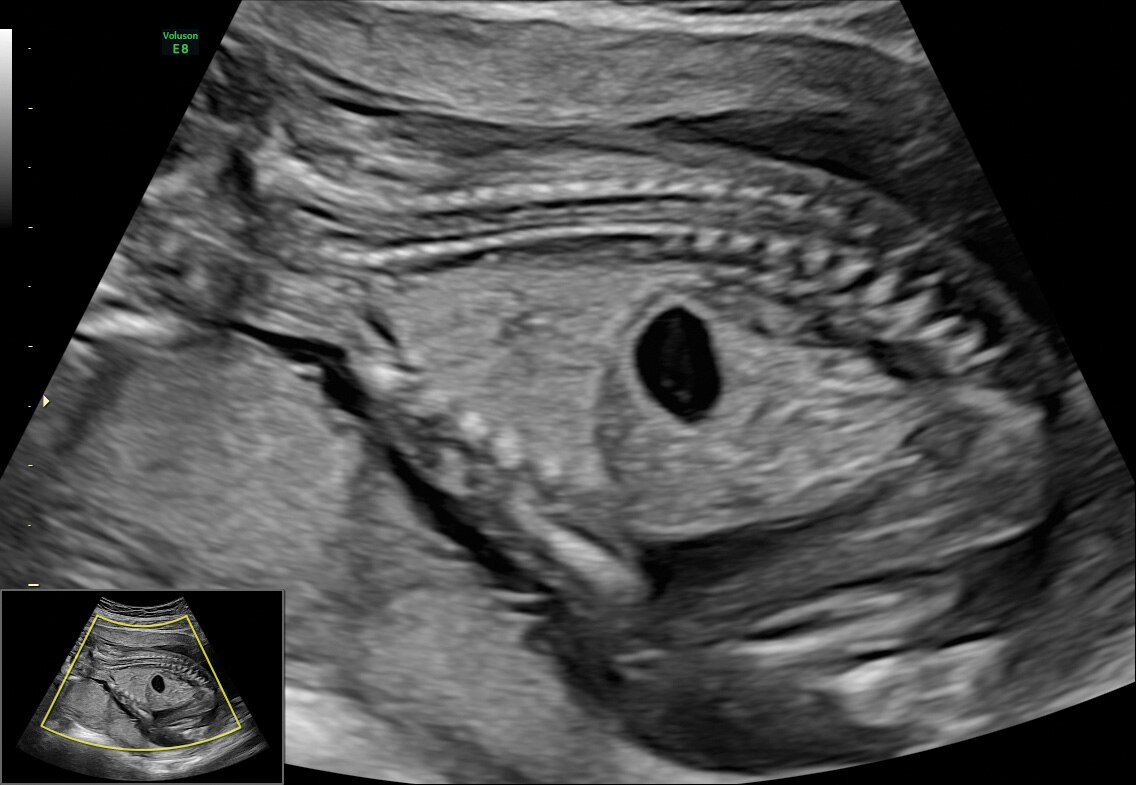

Radiantflow

Atinja um novo padrão de Doppler colorido com o Radiantflow, que oferece uma visualização fácil e rápida até do mais minúsculo dos vasos.